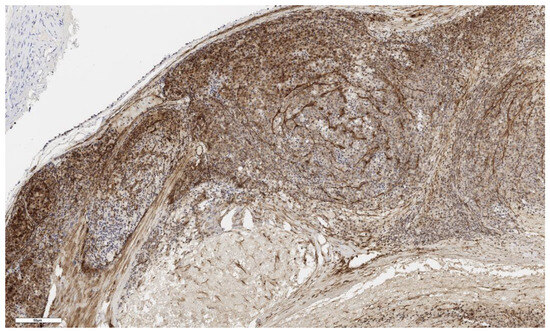

Figure 10.

CD90 expression in normal adrenal tissue, ×100. Scale bar = 300 μm.